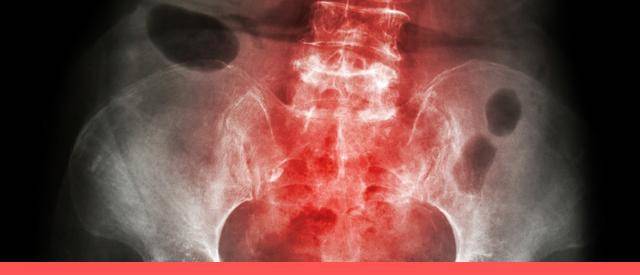

强直性脊柱炎是一种累及脊柱、骶髂关节和髋关节的慢性进展性疾病,疾病早期的病情特点主要表现为腰背部疼痛,夜间痛最为多见,患者因疼痛辗转反侧、彻夜难眠,疼痛难以忍受。

虽然疼痛严重影响生活质量,但强直性脊柱炎带来的最严重问题并不在于疼痛本身,而是在于:强直性脊椎炎侵犯脊柱椎间关节、肌腱、韧带及周围关节的慢性疾病,使关节韧带、软骨等骨化。随着病情进展,骶髂关节和脊柱椎间关节骨化,关节间隙融合,导致脊柱活动度逐渐消失。

一般情况下,强直性脊柱炎的发展从骶髂关节开始,逐渐波及腰椎、胸椎,最后波及颈椎。如果累及腰椎,脊柱将呈板状,医学上称为“板状腰”,弯腰活动将受限,身体的灵活程度将受到影响;如果累及胸椎,胸廓的呼吸运动功能消失,患者将只能依靠腹肌进行呼吸,出现呼吸局促、憋闷等症状,不能适应跑步、跳远等体力运动;如果累及颈椎,患者将无法抬头看天或低头看地,走路容易摔倒。此时,患者的日常生活将受到严重影响,身体犹如一根钢筋,无法扭动腰部或臀部,连正常行动都成为困难,跳舞、打球等运动都将成为令患者向往的过去。

更为可怕的是,部分强直性脊柱炎患者的关节融合并不呈现由骶髂关节向上进展的特征,而是以骶髂关节同时向上下同时进展,在导致脊柱活动度丧失的同时,还导致髋关节活动度消失。医学上主要表现为髋强直,患者不但不能下蹲,而且不能迈步、抬腿,坐凳子、步行、上厕所都将非常困难。